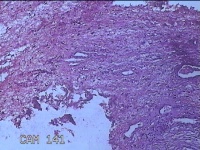

宫颈组织

性别

女

年龄

54岁

临床诊断

宫颈上皮内瘤变Ⅰ级

一般病史

反复阴道脱出肿物3年余。

标本名称

大体所见

灰白暗红色组织4.8x1.5x0.3cm一块,肥大,糜烂,切面灰白粉红色,质软